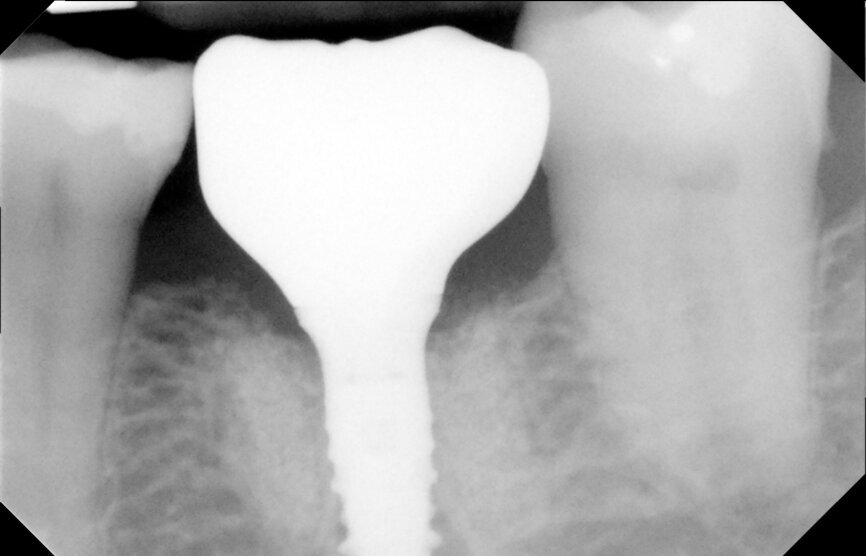

Fig. 3: Tooth #36 initial situation.

After careful assessment of the patient’s anatomical condition through a panoramic radiograph and CBCT scan (Figs. 1–3), it was possible to verify ideal interradicular bone availability, allowing the following treatment plan:

A 68-year-old male patient, a non-smoker, presented with controlled Type 2 diabetes. He had undergone previous dental implant treatments with positive results in the past. The patient presented to the office with tooth #36 in a non-restorable condition with indication for extraction. He requested a dental implant as the treatment choice.